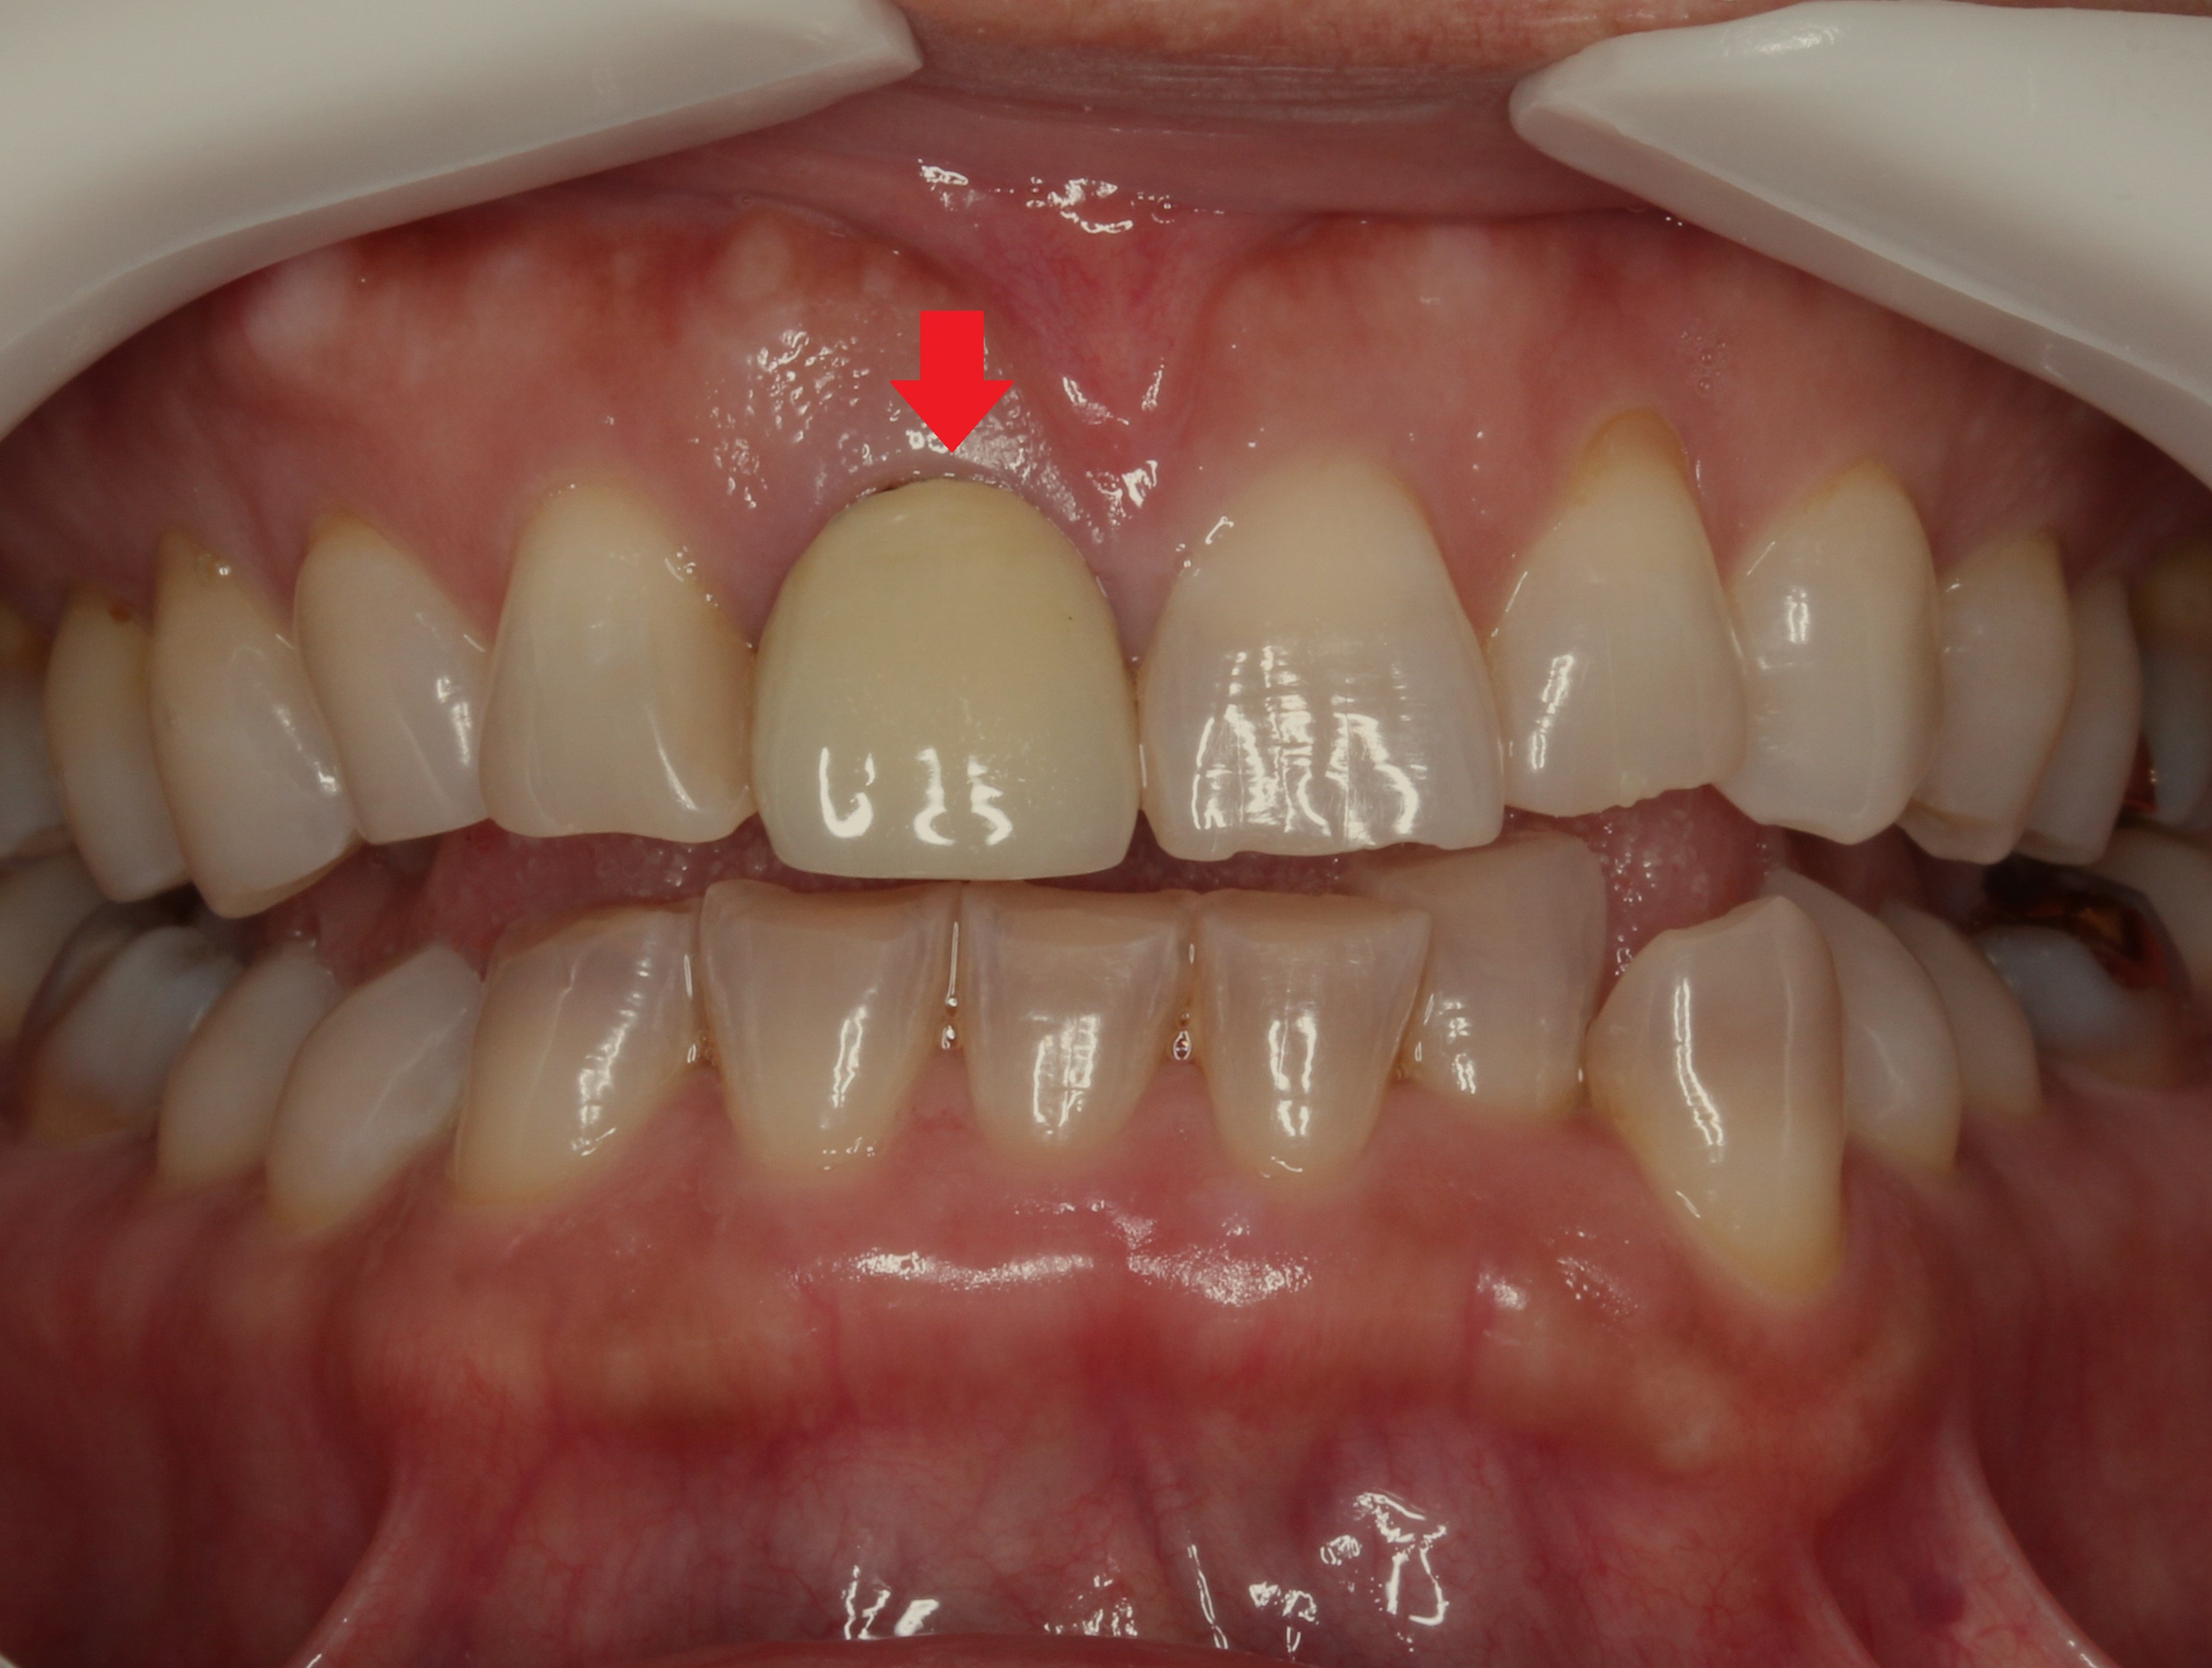

お口の中を見てみると

このような状態でした。

どこが差し歯かわかりますよね?

矢印のこちらの歯です。

歯の根元が黒くなり、

歯の色が合わなく1本だけ浮いて見えます。

また歯の形も膨らみが強く、いかにも「作った歯」という感じです。